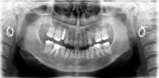

ソケットリフト

右上4(骨が4ミリ弱の厚みで)にソケットリフトを行い骨を持ち上げて10ミリ

のインプラントを埋入する。オペは15分程度で無事終了。

削る量を最小限に慎重に骨を持ち上げて行くためサイナスリフトのように2度オペをせずにすむところが最大のメリットである。